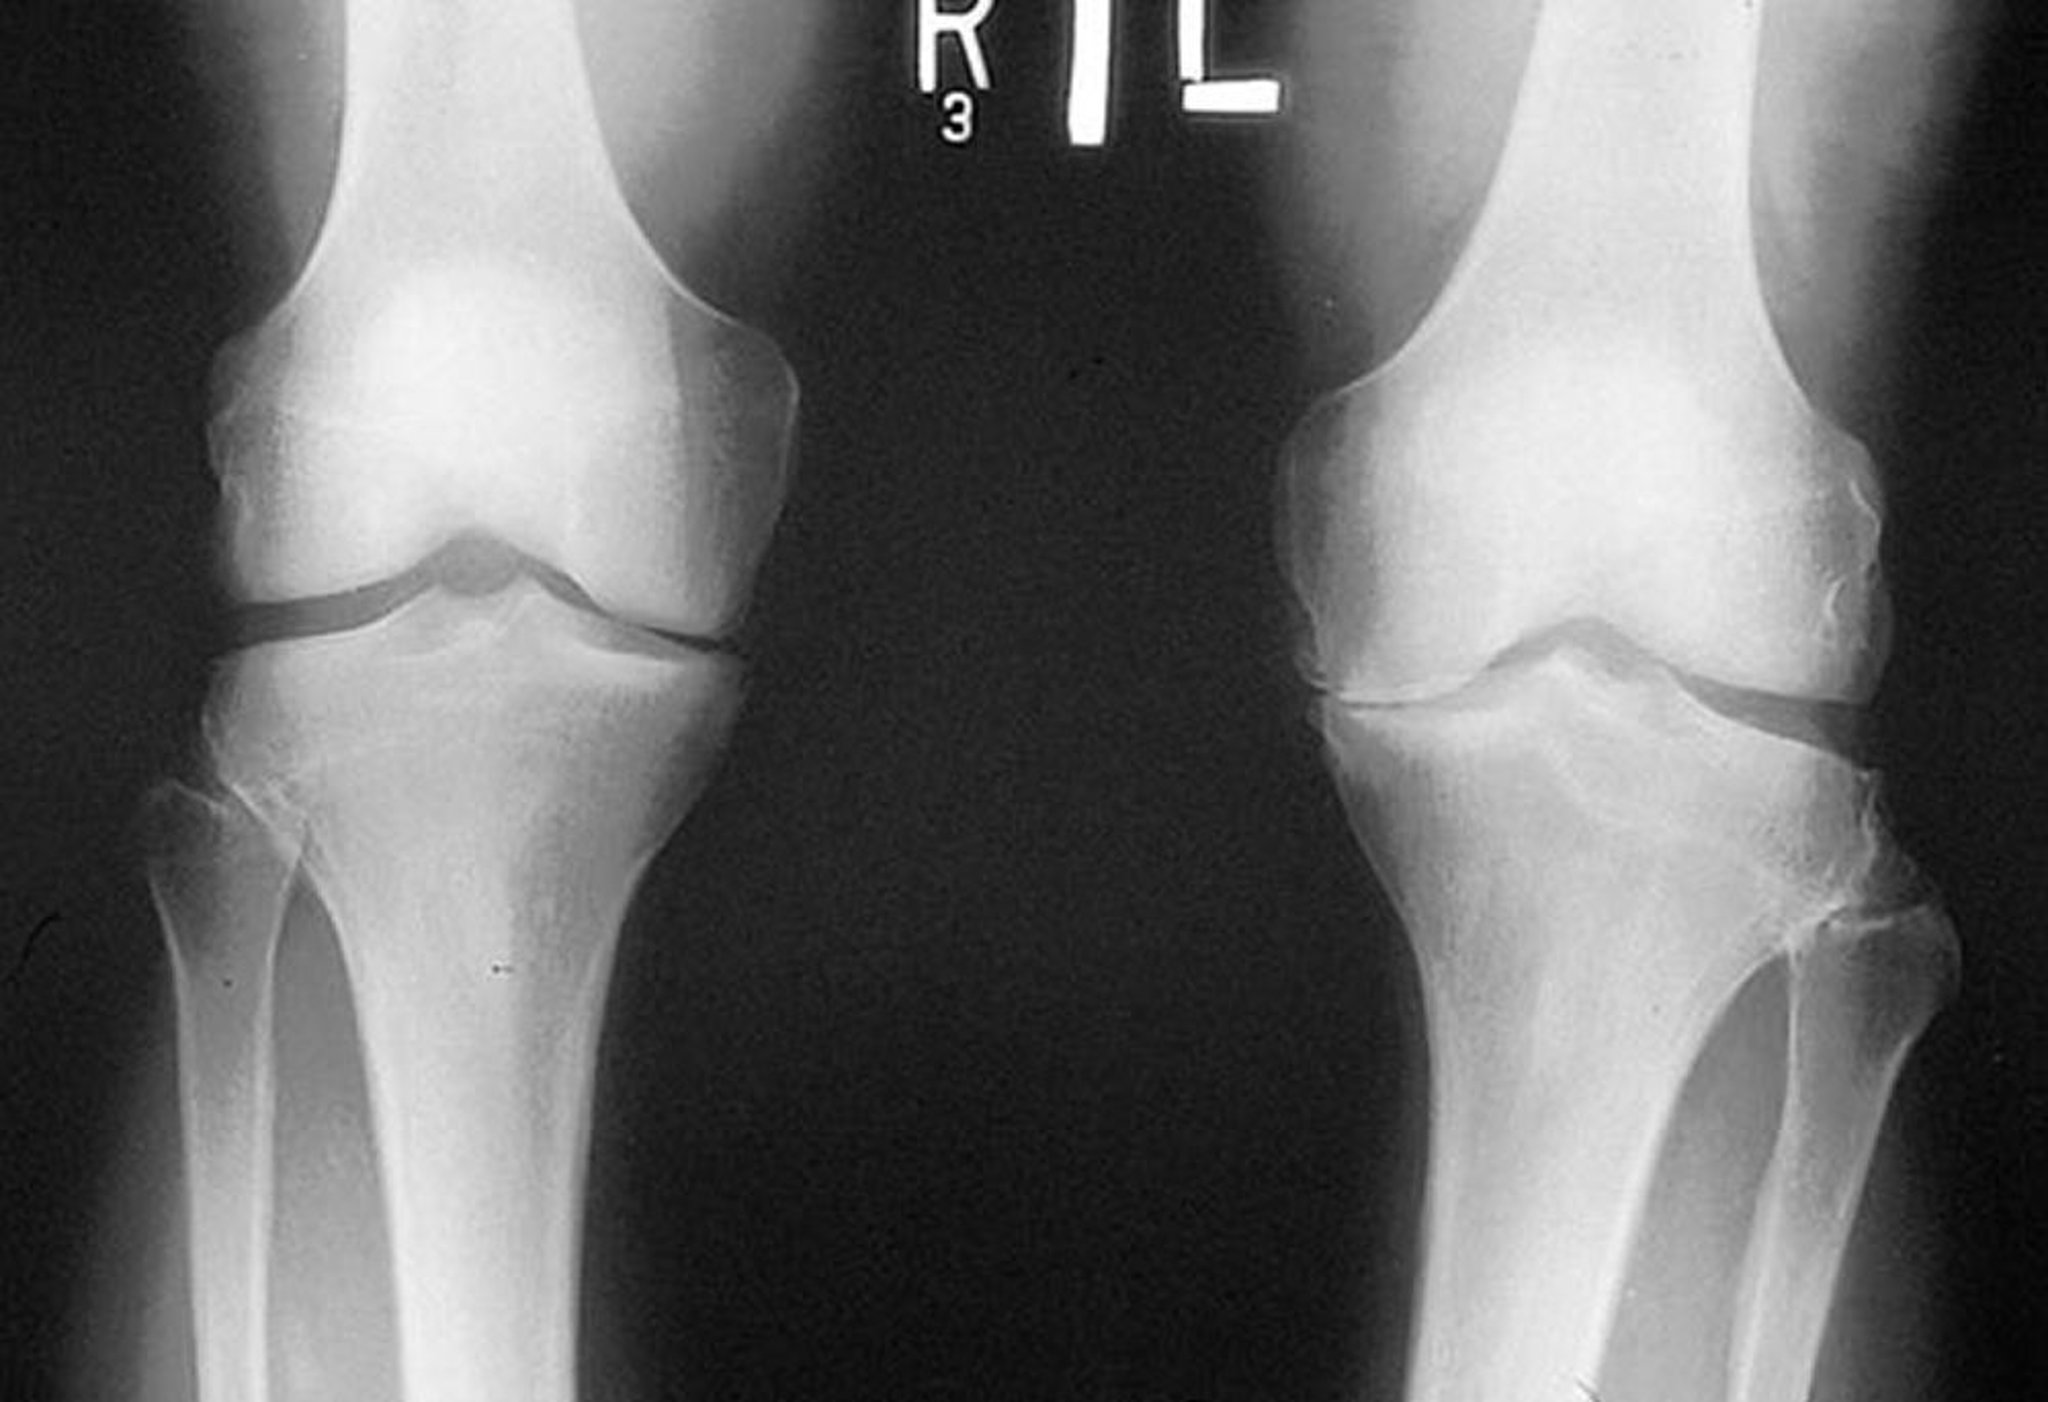

Radiographie du genou dans l'arthrose

Cette radiographie, prise debout, montre que l'espace articulaire fémoro-tibial dans le compartiment médial des deux genoux est étroit, particulièrement à gauche. Des ostéophytes marginaux sont visibles. Il y a usure du plateau tibial médial gauche.

By permission of the publisher. From Myers S: Atlas of Rheumatology. Edited by G Hunder. Philadelphia, Current Medicine, 2005.